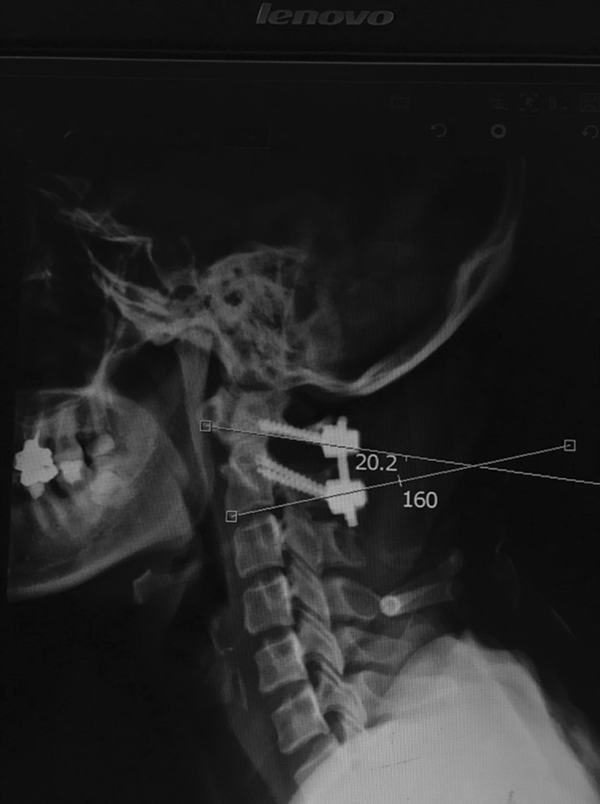

需要手术医师注意的是,正常男性寰枢椎夹角(atlantoaxial angles, AA angles)为26.7±7°,女性为28.9±6.7°。但术中AA角矫正过大,会导致C2-C7间Cobb角减小。而AA角度过小,又会导致复位效果不理想。

有研究指出,术后理想AA角应维持在20°左右,不必过分矫正。此外,手术医师有时为了避免不融合的情况发生,往往会扩大术中暴露及融合的范围,这可能会导致C2-C3也形成骨性融合,从而引起应力过分集中而导致C3-C4之间失稳[9][10]。